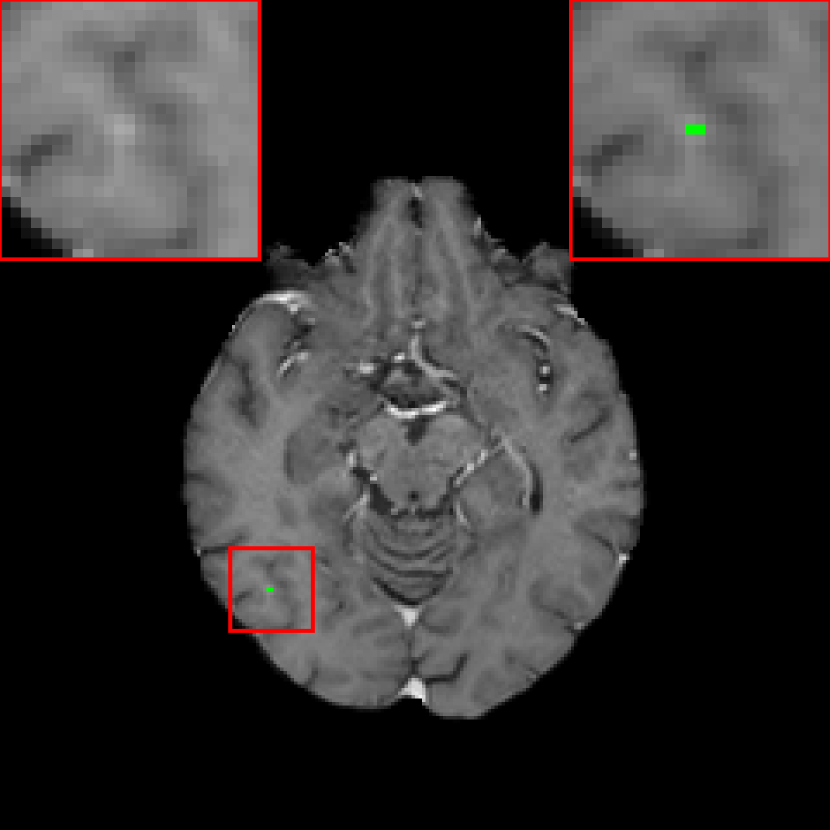

Figure 4: Three examples of FN metastases by baselinesubscriptbaseline\mathcal{M}_{\text{baseline}} (the baseline DeepMedic model trained with BCE loss), which are detected by DeepMedic with the JVSS (α=0.995𝛼0.995\alpha=0.995) loss. The segmentation masks are indicated by green color. Two zoomed-in ROIs without and with the segmentation mask are displayed on the left and right top corners respectively for each patient.

The metastasis-level evaluation of DeepMedic and DeepMedic+ models trained with different loss functions is displayed in Tab. 1. The baseline DeepMedic model achieves a sensitivity of 0.853 (237/278) and a precision of 0.691 (237/(237 + 106)). In other words, among the 278 metastases, 237 TP metastases are detected, while 106 FP metastases are also marked. The FN metastases are mainly tiny metastases, as displayed in the top left regions-of-interest (ROIs) of Fig. 4 where three exemplary FN metastases are displayed.

With the JVSS loss, depending on the value of α𝛼\alpha in Eqn. (4), the sensitivity and precision can be adjusted. When α=1𝛼1\alpha=1 where high sensitivity is desired, DeepMedic achieves a high sensitivity of 0.975 (271/278) but a low precision of 0.275 (271/(271 + 718)). Among all the 278 metastases, 271 are successfully detected, but 718 FP metastases are detected. With a slight smaller α𝛼\alpha value, i.e., α=0.995𝛼0.995\alpha=0.995, a high sensitivity of 0.946 (263/278) is achieved, while the precision is increased to 0.516 (263/(263 + 247)). The number of FP metastases is decreased from 718 to 247. In the top right ROIs of Fig. 4, the metastasis positions of the three exemplary images are correctly detected by DeepMedic trained with the JVSS loss (α=0.995𝛼0.995\alpha=0.995).

In Fig. 4, the volume sizes of the three metastases are all smaller than 0.1 cm3. Therefore, it is very challenging for DeepMedic, and for human experts as well, to identify them, especially with many vascular structures being similar to them. These small metastases consist of very few voxels and there is ambiguity due to partial volume effects in the periphery of the metastases. For such tiny metastases, DeepMedic only detects a few voxels, or even one voxel only, in each metastasis region. For example, in Fig. 4, not all the metastasis voxels are covered by the segmentation mask. Nevertheless, detecting their existence already has important clinical value. In general the segmentation accuracy of DeepMedic does not change or changes slightly for all other large metastases. This is demonstrated by the mDSC values in Tab. 1 and the 3D rendering in Fig. 9. Interestingly, mDSC is even improved using the proposed JVSS loss in senssubscriptsens\mathcal{M}_{\text{sens}} as compared to BCE alone, which illustrates that the introduction of the proposed VSS loss does not compromise the accuracy of individual segmentation masks in detected metastases.